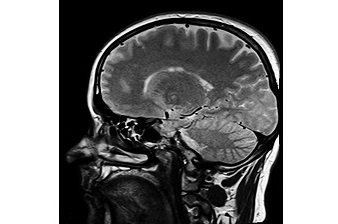

뇌종양은 두개골 안쪽에서 발생하는 종양의 통칭입니다. 뇌종양에는 2종류가 있는데, 폐암 등이 전이되는 '전이성'과 뇌세포나 신경 등에서 발생하는 '원전성'으로 나눌 수 있습니다. 어린이부터 노인까지 다양한 연령대에 발생할 수 있고, 양성과 악성으로 나눌 수 있습니다.

뇌종양이라고 들으면 '더 이상 살 수 없다'거나 '죽음으로 직결된다'는 등 무서운 이미지가 떠오르겠지만, 조기에 발견해서 적절하게 치료를 하면 나을 가능성도 충분히 있다고 합니다. 뇌종양은 초기증상이 나타나는 경우가 많이 있습니다. 갑자기 증상을 자각하고 급격하게 발병한다기보다는 초기증상부터 시작해 종양이 커짐에 따라 서서히 진행된다고 합니다.

뇌종양은 종양이 발생한 부위나 크기에 따라 일상생활이 어려워지거나 생명에 지장을 줄 수 있습니다. 그래서 초기증상을 계속 간과하고 방치하는 것은 매우 위험합니다. 초기 증상을 빨리 깨닫고 적절하게 대처하는 것이 중요합니다.

이 초기 증상에는 뇌종양으로 인해 머릿속 압력이 상승함으로써 일어나는 두개내압항진 증상과 신경을 관장하는 부위에 종양이 생기는 국소 신경학적 증상', 그리고 뇌의 일부가 이상 흥분을 일으키면서 발생하는 경련(경련, 간질) 발작이 있습니다.